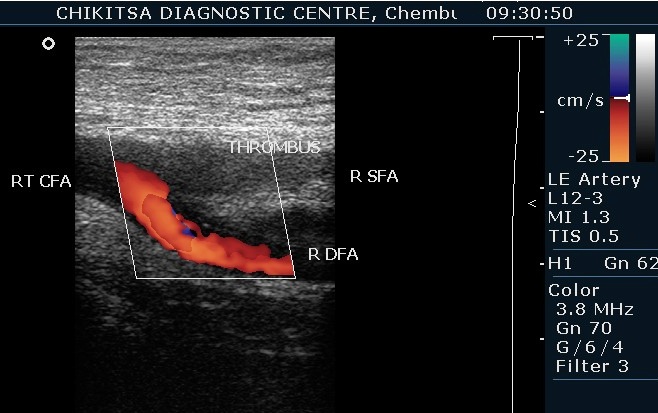

Doppler Studies

Arterial Study of Limbs

This test is used to look at the blood flow in the large arteries. Blood flow in an artery may be compromised due to narrowing of the artery due to atherosclerosis or blockage of the artery due to clotting of blood. A normal result means the blood vessels do not show signs of narrowing or clots and the arteries have normal blood flow.